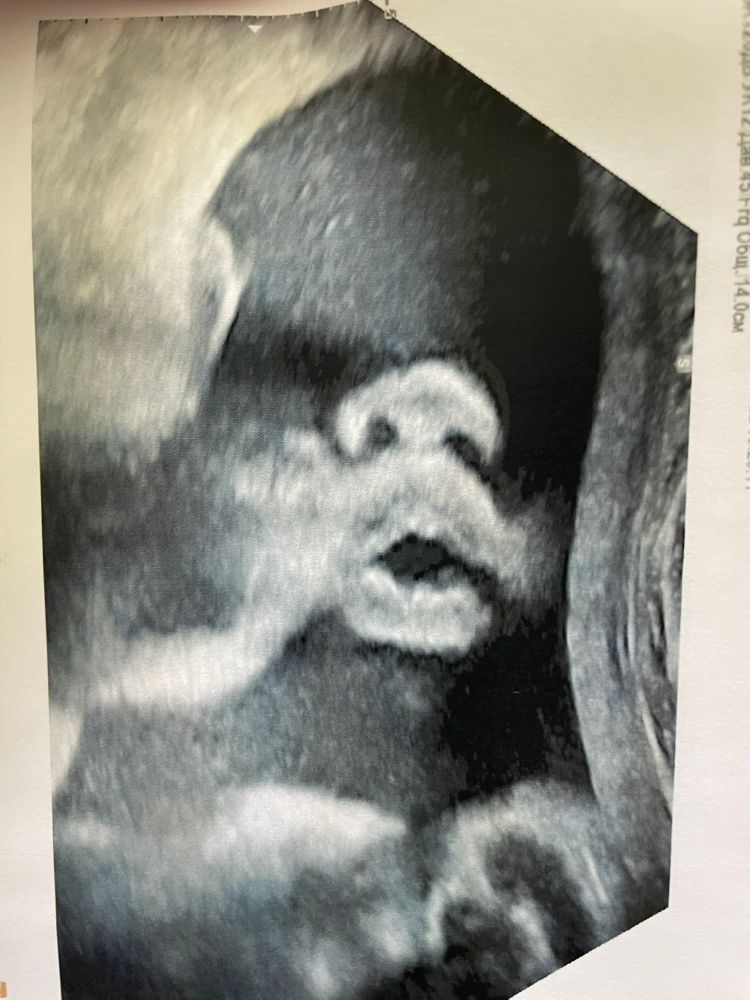

Побежала записываться к Тё С.А. Увидела снова свою куколку ❤️ 32.5 срок, по узи на 33.0. Вес 2300, сказал к родам будет 3600 примерно (а у меня все дети 3540-3610). Воды в норме, по верхней границе, но норма. Ну и никакой макроглоссии. Рубец 3мм, без изменений. Всё, что он смог найти за 50 минут - это возможно киста слюнных желёз под язычком. Но она была очень активная и не дала это опровергнуть.

Ждём встречи 🙏🏻😻🥰